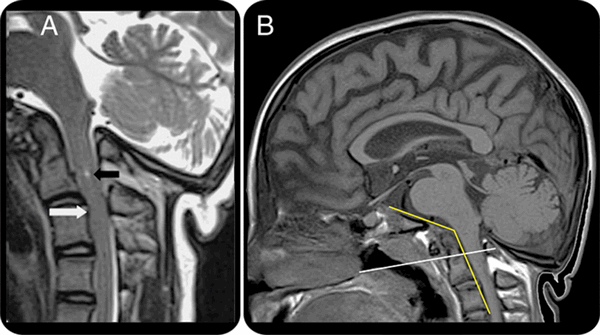

На МРТ краниовертебрального перехода − платибазия и базилярная импрессия при несовершенном остеогенезе